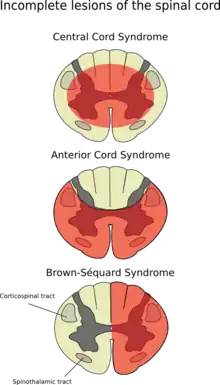

Brown-Séquard syndrome (also known as Brown-Séquard's hemiplegia, Brown-Séquard's paralysis, hemiparaplegic syndrome, hemiplegia et hemiparaplegia spinalis, or spinal hemiparaplegia) is caused by damage to one half of the spinal cord, i.e. hemisection of the spinal cord resulting in paralysis and loss of proprioception on the same (or ipsilateral) side as the injury or lesion, and loss of pain and temperature sensation on the opposite (or contralateral) side as the lesion. It is named after physiologist Charles-Édouard Brown-Séquard, who first described the condition in 1850.[1]

The hemisection of the cord results in a lesion of each of the three main neural systems:

- the principal upper motor neuron pathway of the corticospinal tract

- one or both dorsal columns

- the spinothalamic tract

As a result of the injury to these three main brain pathways the patient will present with three lesions:

- The corticospinal lesion produces spastic paralysis on the same side of the body below the level of the lesion (due to loss of moderation by the UMN). At the level of the lesion, there will be flaccid paralysis of the muscles supplied by the nerve of that level (since lower motor neurons are affected at the level of the lesion).

- The lesion to fasciculus gracilis or fasciculus cuneatus (dorsal column) results in ipsilateral loss of vibration and proprioception (position sense) as well as loss of all sensation of fine touch.

- The loss of the spinothalamic tract leads to pain and temperature sensation being lost from the contralateral side beginning one or two segments below the lesion.

Brown-Séquard syndrome is an incomplete spinal cord lesion characterized by findings on clinical examination which reflect hemisection of the spinal cord (cutting the spinal cord in half on one or the other side). It is diagnosed by finding motor (muscle) paralysis on the same (ipsilateral) side as the lesion and deficits in pain and temperature sensation on the opposite (contralateral) side. This is called ipsilateral hemiplegia and contralateral pain and temperature sensation deficits. The loss of sensation on the opposite side of the lesion is because the nerve fibers of the spinothalamic tract (which carry information about pain and temperature) crossover once they meet the spinal cord from the peripheries.

Any presentation of spinal injury that is an incomplete lesion (hemisection) can be called a partial Brown-Séquard or incomplete Brown-Séquard syndrome.

Brown-Séquard syndrome is characterized by loss of motor function (i.e. hemiparaplegia), loss of vibration sense and fine touch, loss of proprioception (position sense), loss of two-point discrimination, and signs of weakness on the ipsilateral (same side) of the spinal injury. This is a result of a lesion affecting the dorsal column-medial lemniscus tract, well localized (deep) touch, conscious proprioception, vibration, pressure and 2-point discrimination, and the corticospinal tract, which carries motor fibers. On the contralateral (opposite side) of the lesion, there will be a loss of pain and temperature sensation and crude touch 1 or 2 segments below the level of the lesion via the Spinothalamic Tract of the Anterolateral System. Bilateral (both sides) ataxia may also occur if the ventral spinocerebellar tract and dorsal spinocerebellar tract are affected.